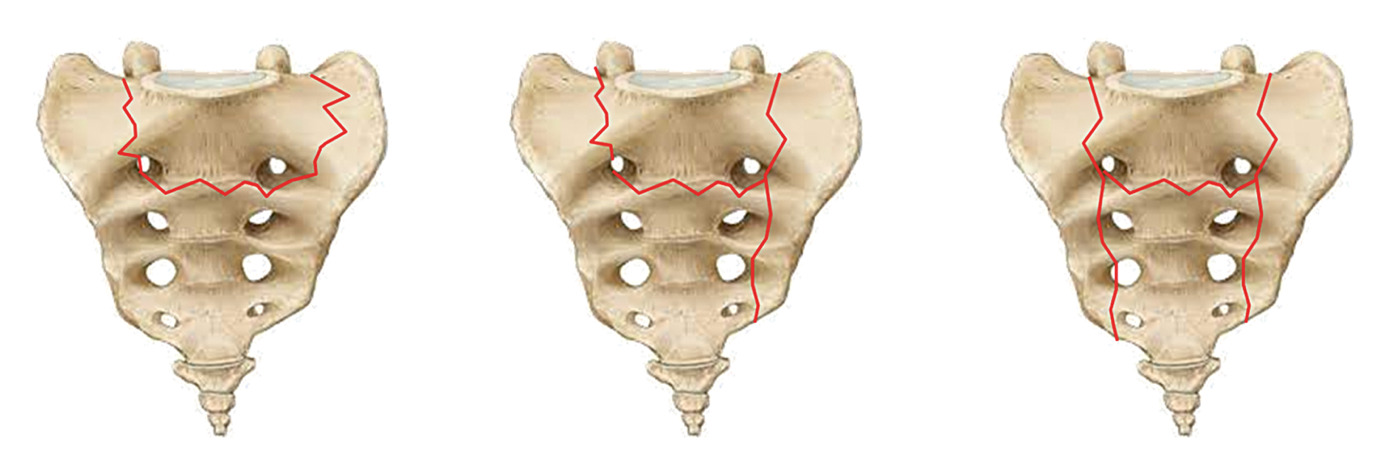

For patients suffering from painful osteoporotic vertebral fractures, surgical options such as vertebroplasty and kyphoplasty offer effective solutions.48,51,53 Vertebroplasty is a minimally invasive procedure where polymethylmethacrylate (PMMA) cement is injected directly into the fractured vertebra to stabilize it and alleviate pain (Figure 5A). Kyphoplasty, an extension of this technique, involves inserting a balloon into the vertebral body before the cement is injected, allowing for the restoration of vertebral height in cases of severe collapse. These approaches can be further enhanced with posterior fixation techniques, which provide additional stability, or with pedicle screw augmentation using PMMA cement (Figure 5B).